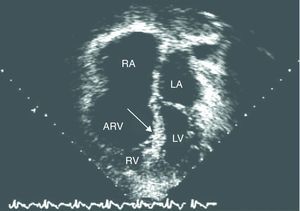

La enfermedad de Ebstein se incluye en el grupo de las cardiopatías cianóticas congénitas con disminución del flujo sanguíneo pulmonar. Se caracteriza por una auriculización de parte del ventrículo derecho y desplazamiento inferior de la válvula tricúspide hacia el ventrículo derecho, con regurgitación tricuspídea. Frecuentemente, el ventrículo derecho es hipoplásico1 (figs. 1 y 2).

Ejemplo de un ecocardiograma (corte de 4 cámaras, ápex inferior) de una paciente con enfermedad de Ebstein severa, en el que se demuestra una valva septal severamente desplazada. La valva anterior está fijada y casi inmóvil. El ventrículo derecho funcional (VD) es pequeño. ARV: ventrículo derecho auricularizado; LA: aurícula izquierda; LV: ventrículo izquierdo; RA: aurícula derecha.